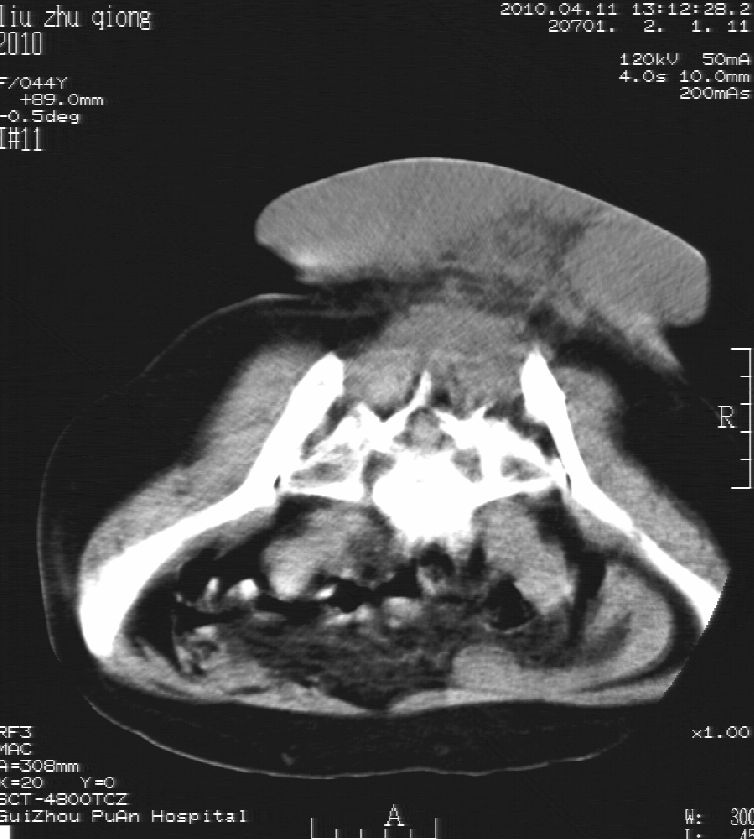

刘某,女,44岁,生第一胎时发现腰背部肿块,黄豆大小,至今17年,呈逐年增大,现行ct检查如下,敬请各位指点。

病史:女,44岁,腰背部肿块,黄豆大小,17年,呈逐年增大。

ct示:骶骨见软组织密度影,似见细条状,或花边状高密度影,考虑不典型钙化灶,向后生长,超出皮肤,可见骶骨破坏,第5幅ct图似与骶管相通。

诊断:脊索瘤

病程长,生长慢,肿块巨大,考虑神经纤维瘤,脂肪密度可以用肿瘤生长过程中包裹入皮下脂肪解释。